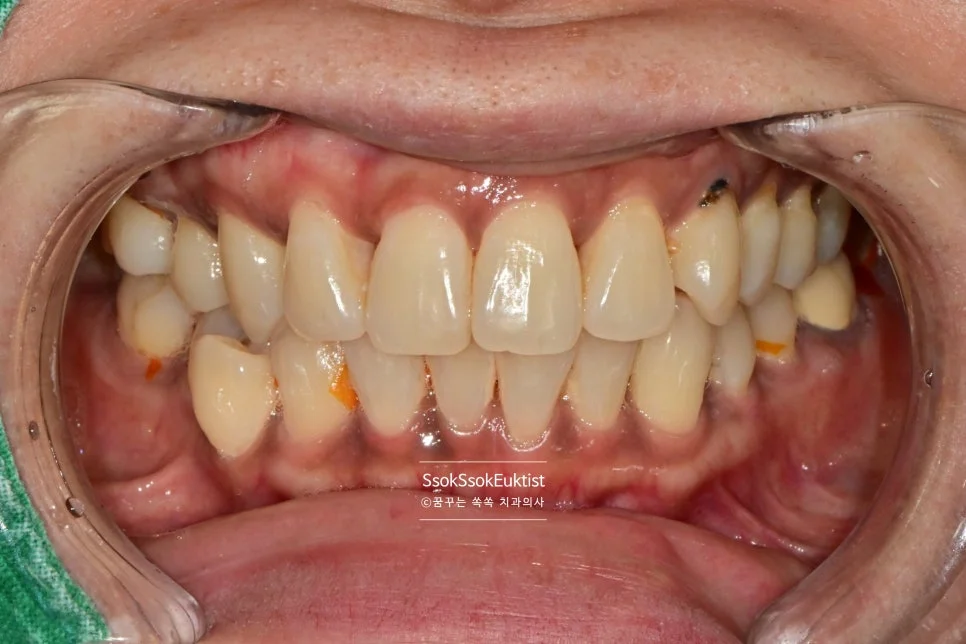

스케일링 전 치석 착색 상태

Before — 스케일링 전

수면 스케일링 후 깨끗한 치아

After — 수면 스케일링 후

왼쪽 위 치경부 우식을 레진으로 예쁘게 치료한 후 스케일링도 시행하였는데요. 비교적 깨끗하고 건강해진 모습이 보입니다~^^